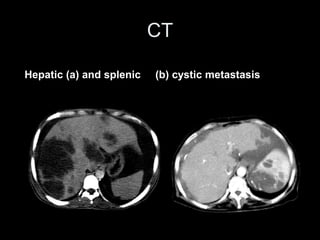

Pseudomyxoma peritonei (PMP) is a rare condition characterized by gelatinous ascites resulting from the rupture of appendiceal mucinous tumors, leading to significant abdominal complications. The incidence is approximately 2 cases per million per year, with a predominance in females, and diagnosis often relies on imaging techniques like ultrasound and CT scans. Effective treatment involves cytoreductive surgery combined with hyperthermic intraperitoneal chemotherapy (HIPEC) to manage disease progression and improve outcomes.